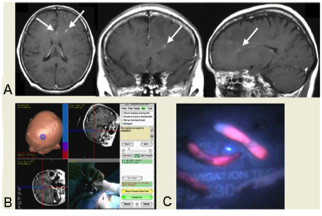

脳の造影剤を用いたMRI検査で特徴的な所見が認められることがありますが、どんな形にもなりうる腫瘍としても有名です。(左図)

(図)ニューロナビゲーションによる腫瘍生検術(穿頭術)

(図)A:MRIで非常に小さな腫瘍がみられます。

B:ニューロナビゲータで生検針を目的の場所に挿入します。

C:採取した組織に青い光を当てると腫瘍は赤く光って見えます(蛍光診断)。